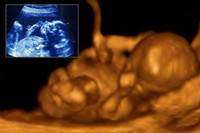

懷孕六個(gè)月胎動(dòng)

懷孕六個(gè)月孕媽已進(jìn)入懷孕中期,這個(gè)時(shí)候最讓孕媽激動(dòng)和不安的事情,應(yīng)該算是胎兒的胎動(dòng)了,很多孕媽有些搞不清楚懷孕六個(gè)月胎動(dòng)是什么樣子的,怎樣的才算是正常的狀況?其實(shí)...閱讀全文>>